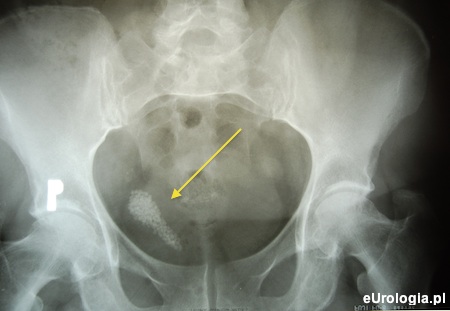

Zdjęcie przeglądowe jamy brzusznej uwidoczniło maczugowaty cień wapienny o wymiarach 60 × 12 mm w miednicy małej po prawej stronie (ryc. 1). Od tomografii komputerowej jamy brzusznej odstąpiono ze względu na awarię aparatu.

Rycina 1. Zdjęcie przeglądowe jamy brzusznej - w miednicy mniejszej patologiczne cienie licznych złogów w rzucie kikuta moczowodu